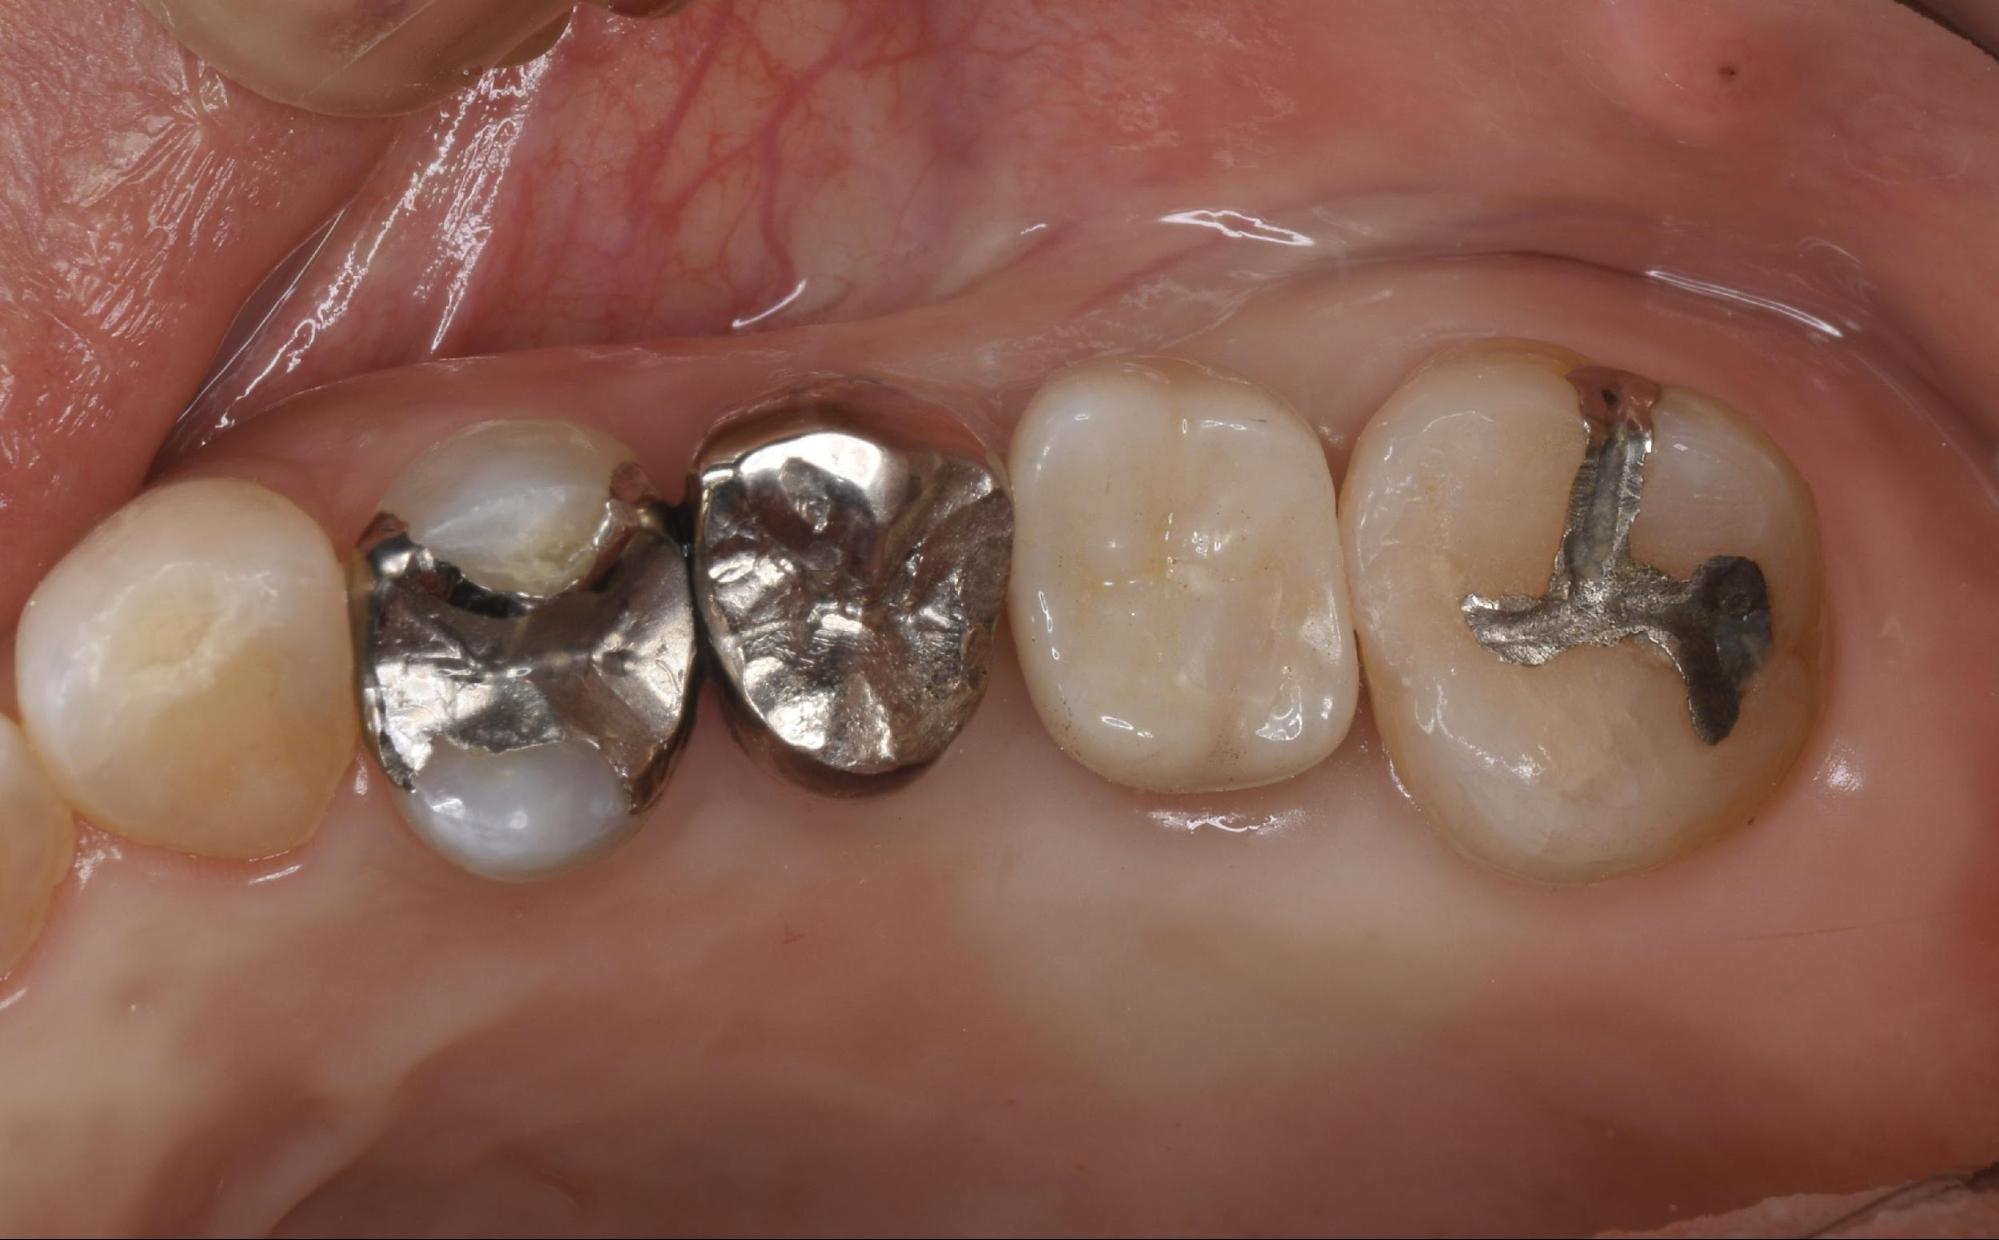

今回は、長年使用していた銀歯の下でむし歯が進行してしまい、抜歯となってしまったケースです。

患者さんは、以前他院で治療された左上の奥歯(銀歯)の痛みを訴えて来院されました。

画像診断の結果、左上の銀歯の下でむし歯(二次カリエス)が重度に進行していることが判明しました。表面の銀歯を一見しただけでは分かりにくいのですが、内部でむし歯菌が感染を広げており、歯の根の方までボロボロの状態になっていました。

一度治療をして詰め物や被せ物(銀歯など)をした歯が、その内側で再びむし歯になってしまうことを「二次カリエス」と呼びます。

銀歯などの保険適用の金属は、経年劣化により接着剤が溶け出したり、金属自体が変形したりすることで、歯との間に目に見えない隙間が生じやすくなります。そこからむし歯菌が侵入し、気づかないうちに内部でむし歯が進行してしまうのです。神経を抜いている歯の場合、痛みを感じにくいため、発見が遅れ、今回のように抜歯を余儀なくされるケースも少なくありません。

まずは問題となっている銀歯を外しました。すると、事前のCT診断で想定していた通り、内部のむし歯は重度に進行しており、歯質のほとんどが失われていました。